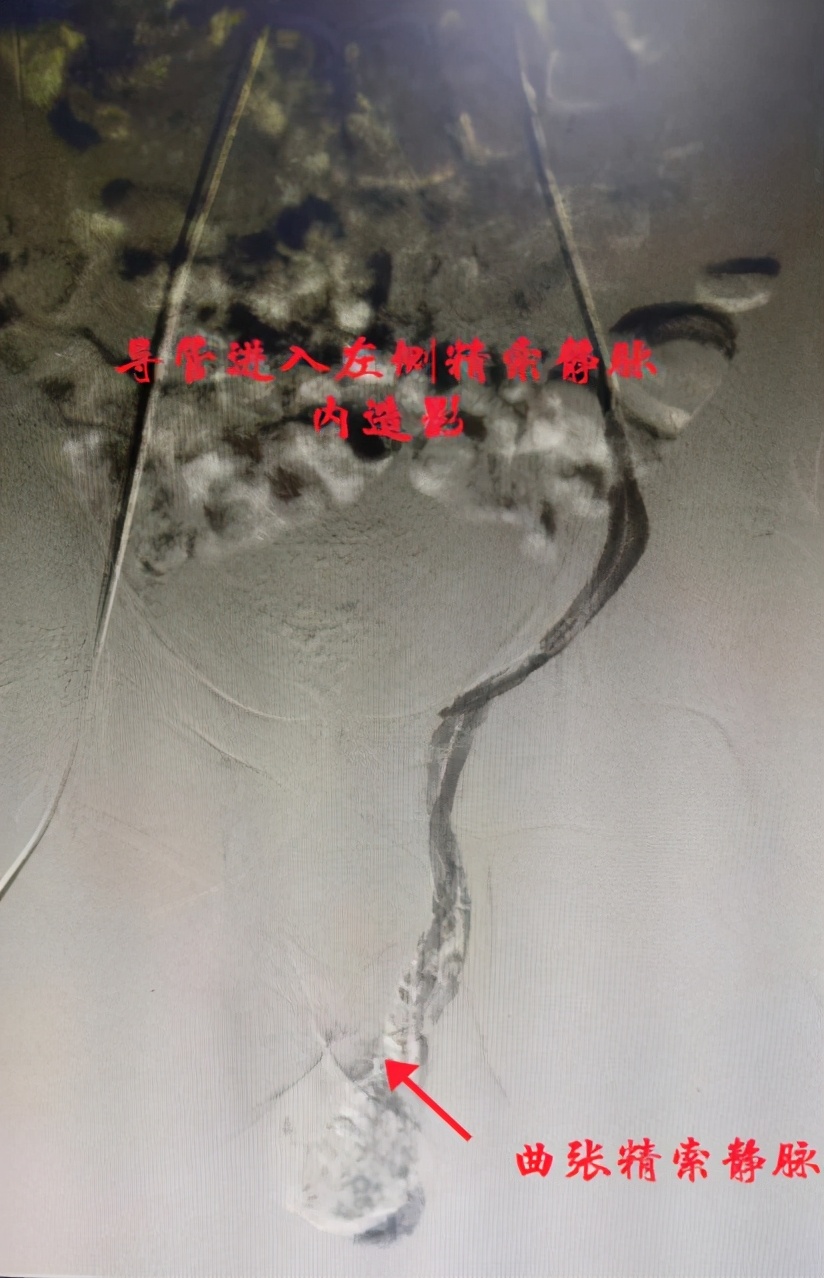

这天小张一大早便找到了自治区南溪山医院血管外科副主任胡长付,在胡主任的耐心解说下小张忐忑的内心终于平静下来。“我们将使用小小的穿刺针穿刺股静脉,送入导管至精索静脉内,”胡长付主任说道:“使用一种药物注入栓塞,便可治疗曲张精索静脉,手术后只留一针尖大小穿刺点,不留疤痕。”

术后曲张精索静脉消失

术前可见曲张精索静脉